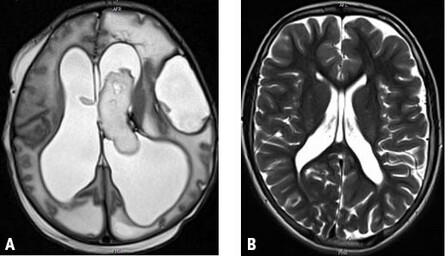

Beides führt zur Schädigung der periventrikulären weißen Substanz. Da die Bahnen zu den Beinen näher am Ventrikel liegen als die zu den Armen, sind so verursachte ICP in aller Regel beinbetont. Finden sich eine Monoparese eines Arms oder armbetonte Paresen, ist an andere Schädigungen, z. B. einen konnatalen Mediainfarkt oder Hirnfehlbildungen, zu denken. Bei bereits intrauterin aufgetretenen Blutungen muss differenzialdiagnostisch an Mutationen in Kollagen-IV-Genen (COL4A1 o. COL4A2) gedacht werden (Abb. 3 A). Bei älteren Kindern mit ICP und nicht eindeutig auffälliger Perinatalanamnese können Erweiterungen und/oder Unregelmäßigkeiten der Ventrikelwände sowie Blutungsreste bei Verwendung sog. Häm-sensitiver Sequenzen in der Magnetresonanztomographie auf stattgehabte Blutungen hinweisen und so den V. a. eine frühkindliche Hirnschädigung erhärten (Abb. 3 B).

Abb. 3 A + B: Kernspintomographisch deutliche Aufweitung der Seitenventrikel mit bereits intrauterin aufgetretener intraventrikulärer Blutung links und zusätzlichem Hämatom linkshemispheral bei einem Neugeborenen mit COL4A1-Defekt (A). Unregelmäßige Begrenzung und posteriore Erweiterung der Seitenventrikel bei einem 12-jährigen Mädchen mit spastischer Diparese sowie Z. n. Frühgeburt in der 31. SSW ohne eindeutig auffällige Perinatalanamnese (B).